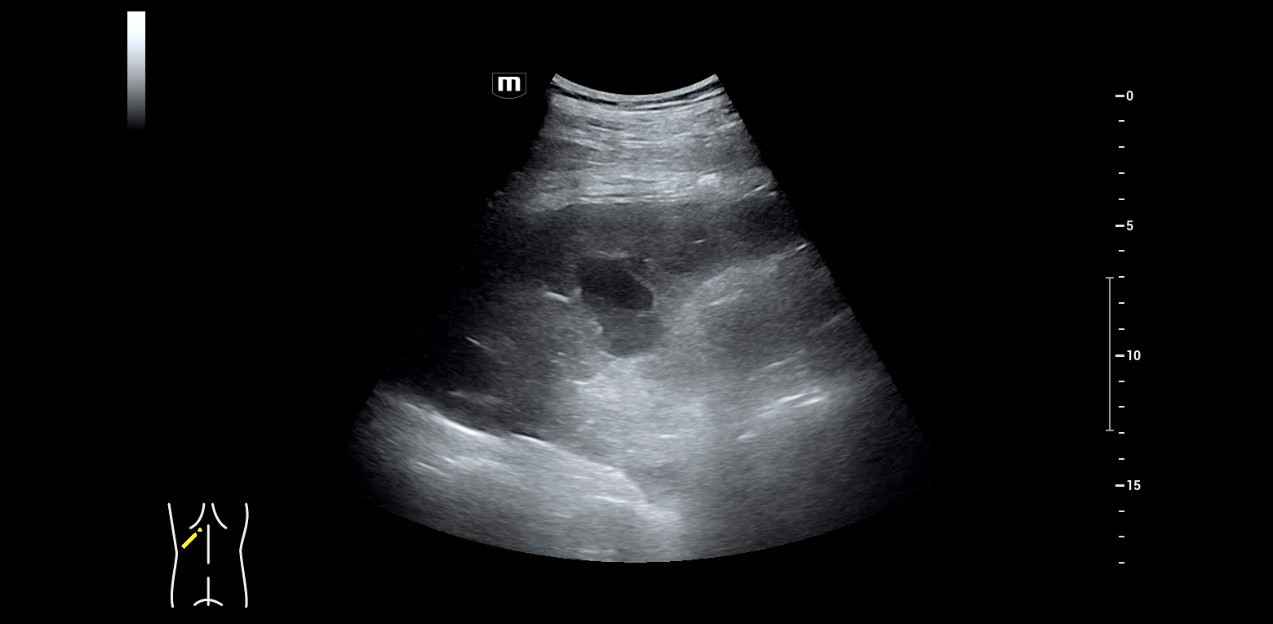

3. Patient with unclear shortness of breath, in the image a primarily unclear peripheral consolidation area of the lung.

4. The contrast agent sonography shows missing perfusion in the same area as evidence of a peripheral pulmonary artery embolism.